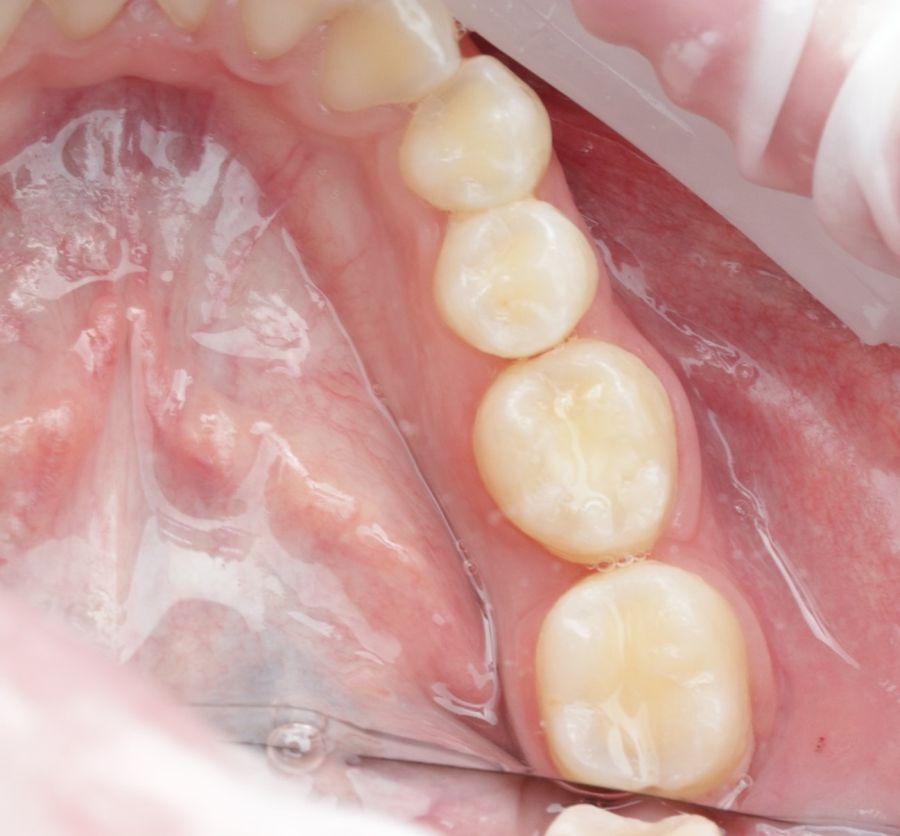

Se reporta el caso de un autotrasplante del tercer molar inferior derecho al alveolo postextracción de un primer molar inferior, en una paciente de 22 años de edad. Actualmente, el autotransplante se considera una opción de tratamiento si se siguen los criterios de selección del caso adecuados, y se realiza una técnica quirúrgica protocolizada. El diagnóstico planificado mediante CBCT, la simulación virtual y la confección de una réplica en 3D optimiza la técnica de forma segura, predecible con tiempos de cirugía menores.

La confección de la réplica 3D del diente se ha de realizar con material biocompatible y esterilizable mediante radiación gamma y beta. La ventaja del modelo estereolitográfico es minimizar el tiempo extraoral del diente donante, el daño al ligamento periodontal, así como poder remodelar el alveolo receptor sin usar el diente donante5,13,14.

Todo ello favorece un crecimiento esquelético continuo y resistencia a las cargas oclusales8,12.